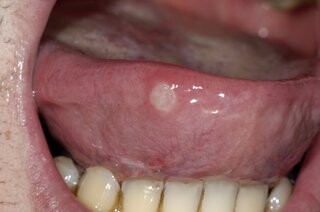

Apthous Ulcers (Canker Sore)

A white spot on the tongue surrounded by a red, inflamed halo is probably an apthous ulcer, more commonly referred to as a canker sore. Aphthous ulcers is a painful inflammatory condition that occurs in the oral soft tissue and on the tongue - often as one or more oval/round or well-defined, grey-yellow ulcerations surrounded by redness..

These common and recurring lesions can be small or large and appear on their own or in groups. Canker sores are often painful, and scraping doesn't remove them.